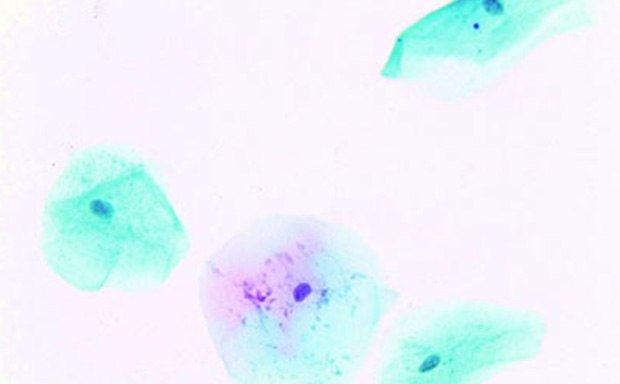

巴氏染色(Papanicolaou,Pap染色)是由George N. Papanicolaou博士开发的广泛使用的细胞病理学染色技术。我们提供一系列的巴氏染色染料和溶液用于细胞各种成分的鉴别染色,以对细胞核和细胞质成分进行严格检查。常见细胞学样本包括阴道、宫颈、前列腺和其他身体分泌物的脱落细胞。巴氏染色液提供手动和自动方法的多种包装选择。核染液包括一系列苏木精溶液和干染料。

采用改良溶液(CYTOCOLOR™)的Szczepanik标准细胞学染色主要用于妇科疾病的早期识别筛查。这些染色剂可在3-4分钟内给出妇科检查涂片有关细胞变化、激素状态和阴道菌群的可靠信息。与传统的巴氏染色法相比,CYTOCOLOR™试剂盒不需要桔黄色染色剂;成熟细胞和角化细胞均呈现粉红色而不是桔黄色。